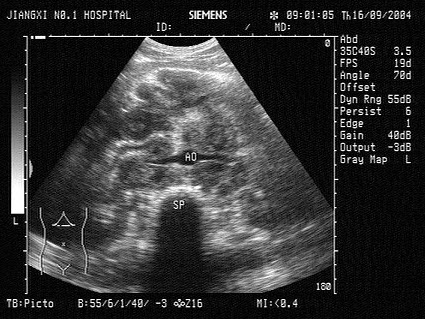

56、单项选择题

患者,急性胰腺炎治疗后,超声见胰管内多个强回声光团,后伴声影,如图所示,考虑为()

A.胰腺胰管结石

B.胰腺脓肿

C.胰腺肿瘤

D.胰腺假性囊肿

E.胰腺胰管钙化